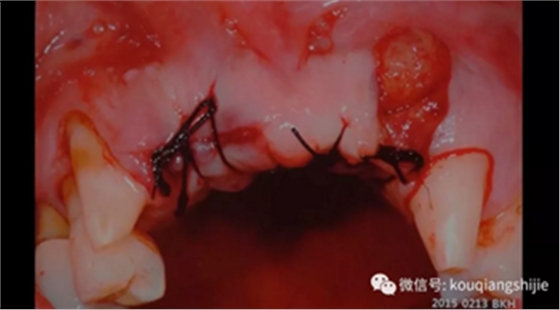

我们将覆盖在拔牙创的线性黏膜组织拉上来,在黏膜与骨之间形成充分的修复空间。

术后恢复情况

当黏膜组织愈合良好之后,再进行进一步种植,并对不足的部分进行进一步修整。